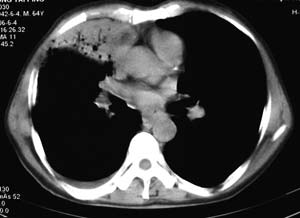

右侧胸廓略小于左侧,右肺上叶大片实变影,近肺门处密度较高,内见支气管气相,周围较淡,呈网格状,余肺野清晰,纵隔内见肿大淋巴结,右侧胸腔少量积液。临床 咳血,咳痰 发热 , 血象1.2万。

考虑大叶性肺炎。

右侧胸阔塌陷,纵隔右移。右上肺大片状高密度影,沿支气管血管束走行,内见点状钙化;支气管充气征阳性,支气管呈柱状扩张;胸膜下小叶间隔增厚;右侧后胸壁内侧见带状水样密度影;纵隔淋巴结增大。

考虑:①右上叶陈旧性结核合并感染可能大。②右侧少量胸水。